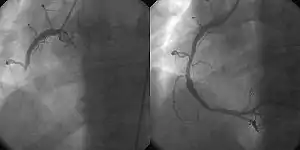

![]() A coronary angiogram showing the circulation in the left coronary artery and its branches. | |

Percutaneous coronary intervention (PCI) is a minimally invasive non-surgical procedure used to treat narrowing of the coronary arteries of the heart found in coronary artery disease.[2] The procedure is used to place and deploy coronary stents, a permanent wire-meshed tube, to open narrowed coronary arteries. PCI is considered 'non-surgical' as it uses a small hole in a peripheral artery (leg/arm) to gain access to the arterial system, an equivalent surgical procedure would involve the opening of the chest wall to gain access to the heart area. The term 'coronary angioplasty with stent' is synonymous with PCI. The procedure visualises the blood vessels via fluoroscopic imaging and contrast dyes. PCI is performed by an interventional cardiologists in a catheterization laboratory setting.[3]